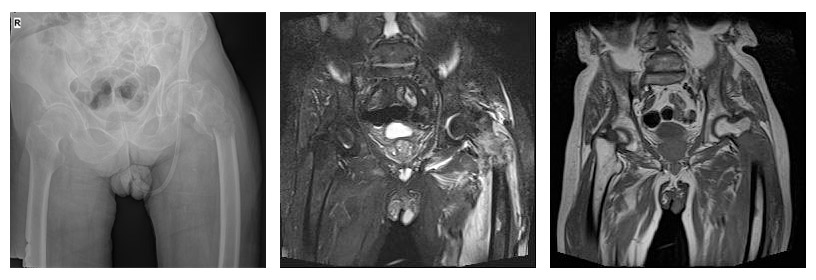

CASE 30: Fracture due to bladder cancer metastasis to the left hip (proximal femur).

Before the surgery: X-ray and MRI show a fracture, displacement, and surrounding edema in the left hip (proximal femur) bone.